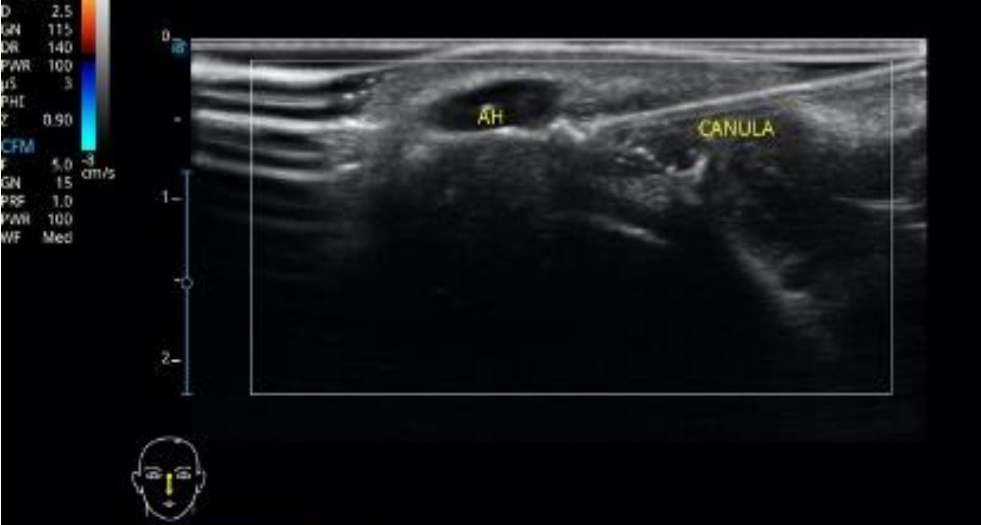

Tábada Bertani • 21/03/2025

Hialuronidase guiada para ultrassonografia

A hialuronidase guiada por ultrassonografia é uma técnica utilizada em procedimentos estéticos espec...